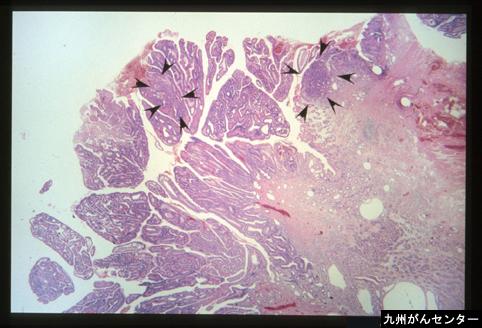

Criteria of Hist.ClassificationMalignant epithelial tumor/Adenocarcinoma

LocationDuodenum/First portion, bulb

Macroscopic TypesType 0/I (Ip) Pedunculated type

Size20 - 24

Depth of Tumor Invasionmucosa